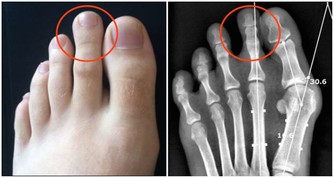

6. 腎結石

腎結石是鈣、礦物質和酸鹽的沉積,當它們滯留在輸尿管時,會引起疼痛并阻礙尿液排出。這種疼痛通常在晚上或清晨很嚴重,可能是因為這段時間的尿量很少。